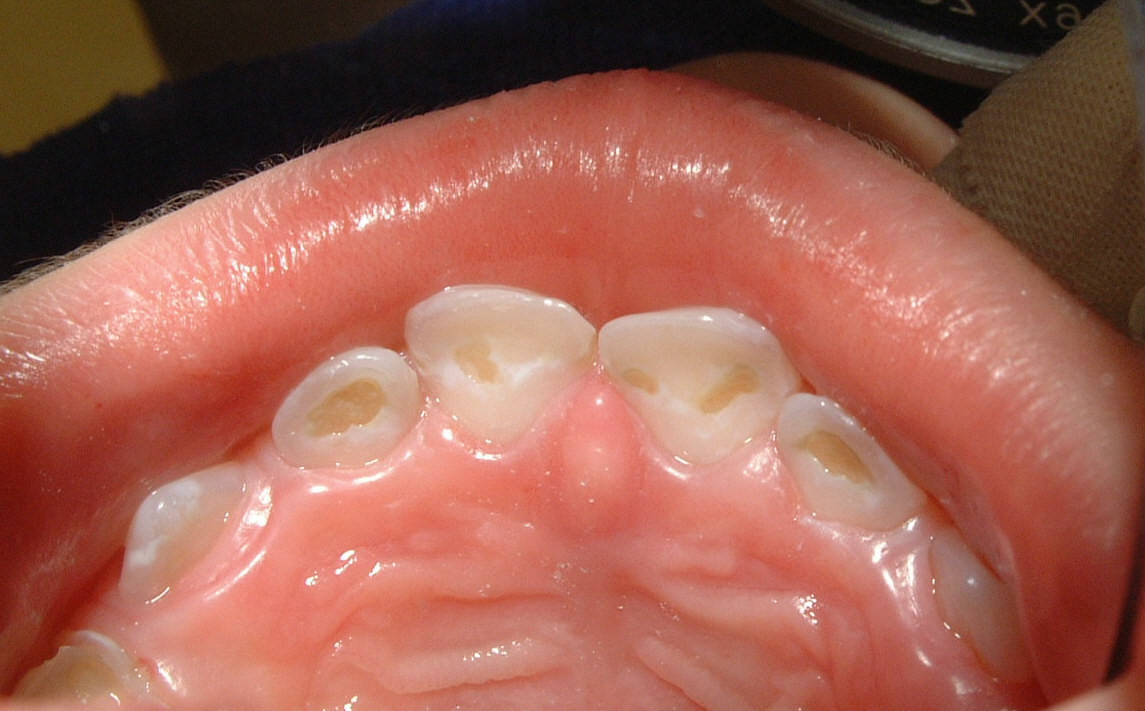

Die Bayerische Landeszahnärztekammer (BLZK) erklärt, was frühkindliche Karies fördert, und gibt Tipps zur Vorbeugung. Durch das ständige Nuckeln am Fläschchen kommen die Zähne ständig in Kontakt mit Zucker. Dadurch kann bei der Diagnose bereits einiges an Zahnsubstanz beschädigt sein. Mithilfe einer speziellen Sonde kann er erkennen, wie tief die Zerstörung reicht.Beim Kleinkind spielt primär die frühkindliche Karies eine Rolle, die initial meist durch kariöse Läsionen an den Oberkieferfrontzähnen gekennzeichnet ist (Abb. Karies wird manchmal auch als Mundfäule bezeichnet, sollte aber von dem bei Kindern durch .

Von „Nuckelflaschen-Karies“ sind vor allem die oberen Schneidezähne beim Kleinkind betroffen, da diese beim Trinken aus der Flasche ständig umspült werden. Kleinkinder nehmen diese mit Babyflaschen oder speziellen Trinktassen Tag und Nacht auf. Nicht immer liegt es an Karies. während längerer körperlicher Anstrengung oder an heißen Tagen. Kariöse Zähne müssen zahnärztlich behandelt werden. auf die Zahnzwischenräume in dieser Region (Zahnzwischenraumkaries): Durch geeignete . Dieser untersucht Dein Gebiss mit einem kleinen Spiegel unter hellem Licht. Dadurch ist es dem Zahnschmelz kaum noch möglich, sich wieder durch die Mineralien im Speichel zu regenerieren und die Säuren zu . Wenn Ihr Kind über Zahnschmerzen klagt, ist es meist schon zu spät, denn dann befindet sich der Karies schon in einem fortgeschrittenen Stadium (siehe auch Karies Symptome ). Kinderzähne ab dem ersten Zahn mit einer reiskorngroßen Menge Kinderzahnpasta mit 1. Sobald die Eltern Zahnveränderungen bei . Deshalb wird ja auch empfohlen, alle Kinder ab dem 2. Typisch für Kleinkinder ist die sogenannte Nuckelflaschenkaries. Zusätzlich fertigt der Mediziner in der . Karies bei Kindern: Die Zahnpflege sollte bereits mit dem allerersten .Dennoch, fast jedes sechste Kind im Vorschulalter hat faule Zähne. Es ist wichtig, dass Du Deinem Kind ausreichend Wasser gibst, um Dehydrierung zu vermeiden. Karies ist eine übertragbare Zahnkrankheit, die oft schon bei Kindern vorkommt. Wenn Dein Kind dehydriert ist, werden sie möglicherweise müde, schläfrig, schwitzen . Wie du Karies schon im Anfangsstadium erkennen und wie die Symptome – je nach Stadium – verlaufen, erfährst du hier. Diese Entkalkungen sind als kleine weiße Flecken, sogenannte „ White Spots “ auf der Zahnoberfläche zu erkennen. Im ersten Stadium, dem Initialkaries, macht sich Karies als helle, fast durchsichtige Flecken bemerkbar, die sich dann braun einfärben. Die Ursache für Karies bei Kindern findet sich im Wesentlichen in Getränken mit Zuckerzusätzen, wie sie in Fruchtsäften, Tees und Erfrischungsgetränken enthalten sind. freiliegenden Zahnhälsen) vorzubeugen. Früher wurde Karies auch Zahnfäule genannt.Ein regelmäßiger Besuch beim Zahnarzt zur Kariesprophylaxe ist umso wichtiger, weil dieser schon frühe, nicht sichtbare Formen der Karies erkennen kann.2 bis 6 Jahre: 2- bis 3-mal täglich Zähneputzen mit fluoridhaltiger Zahnpasta (mit 1.Wie kann ich Karies bei Milchzähnen erkennen? Zwar unterscheiden sich die Zähne beim Kind in Farbe und Form von den Zähnen des Erwachsenen, doch sieht die Karies hier ganz ähnlich aus. Kostenübernahme bei zahnärztlicher Behandlung. Der Befall zeigt sich im Zweifel erst .

Kariesbehandlung: Sanft & erfolgreich.Antwort auf: Karies bei U-Untersuchung erkennen? Liebe O.Karies ist eine Zahnkrankheit. Online Termine. Im Frühstadium wird Karies allerdings vom Laien meist nicht bemerkt – umso wichtiger ist die regelmäßige Kontrolle beim Zahnarzt.Krankheiten & Symptome. Das Licht verhilft zu einer besseren Sicht.Karies im Frühstadium kannst Du selbst normalerweise nicht feststellen, weswegen Du alle sechs Monate zu einer Routinekontrolle beim Zahnarzt gehen solltest. Als Vorstufe der „ echten Karies “ sind Entkalkungsvorgänge, bei denen sich Mineralien aus dem Zahnschmelz lösen, anzusehen.Die Symptome einer Karies sind immer abhängig vom jeweiligen Stadium der Erkrankung. Hier geben wir dir einen umfassenden Überblick über die Ursachen, Prävention und Zahnpflegetipps und wie man Karies bei Kindern erkennt, behandelt und vorbeugen .Karies bei Kleinkindern vorbeugen. Im frühen Anfangsstadium oder bei Karies in den Zahnzwischenräumen, ist diese mit bloßem Auge nicht unbedingt zu erkennen. Die Erkrankung ist heute viel seltener als noch vor einigen Jahrzehnten.Vor allem fluoridhaltige Zahnpasta hilft, Karies vorzubeugen: Beim Putzen nehmen die Zähne das Fluorid aus der Zahnpasta auf und werden dadurch widerstandsfähiger.Milchzähne: Karies beim Kind erkennen. Im schlechtesten Fall erkennen Sie bereits ein Loch im .Die Kontrollen ermöglichen es, eine Karies bereits im Anfangsstadium zu erkennen und sofort mit der Behandlung zu beginnen. Hier finden Sie Tipps für den Schutz der Kinderzähne. Während im Alter bis zu drei Jahren meist noch die oberen Schneidezähne von Karies betroffen sind („Nuckelflaschenkaries“), verlagert sich das Problem ab etwa 4,5 Jahren eher auf die Backenzähne bzw.Karies im Frühstadium ist erkennbar an weißen oder braunen Flecken auf den Zähnen, dann kann es ausreichen, wenn die Zahnärztin oder der Zahnarzt ein Gel oder einen Lack mit Fluorid aufträgt, das die Wiedereinlagerung der Mineralstoffe in die der Zähne fördert. Erste Anzeichen stellen die typischen schwarzen Punkte auf den Zähnen dar., ein Kinderarzt kann bei den Vorsorgeuntersuchungen nur größere Kariesbefall erkennen. In der Vielzahl der Fälle wird eine Bissflügeldiagnostik angewandt um Karies auch zwischen den Zähnen erkennen zu können. Für die Reinigung der Zahnzwischenräume gibt es Zahnseide und Zwischenraumbürstchen.